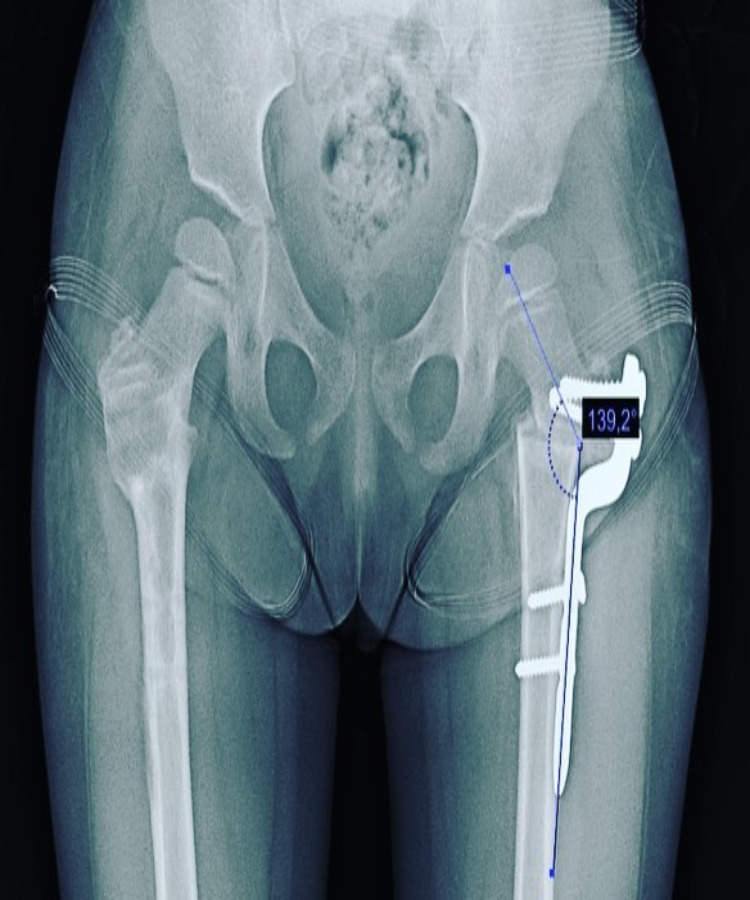

conocer másLas deformidades de pie y rodilla incluyen genu varo, genu valgo, pie plano y pie cavo, con causas congénitas o postraumáticas.